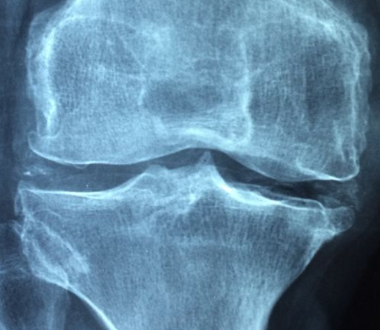

콘드로이친은 연골 조직에서 발견되는 주요 성분 중 하나로, 그리고 연골 조직의 건강을 유지하는 데 중요한 역할을 합니다. 연골 조직은 관절에서 뼈를 보호하고 충격을 흡수하는 역할을 하며, 노화 및 손상으로 인해 연골은 탄력과 강성을 잃어 골퇴화 및 연골파괴로 이어질 수 있습니다.

연골은 우리 몸에서 뼈와 관절 사이에 있어서 충격을 완화하고 뼈를 보호하며, 관절 운동을 부드럽게 합니다. 콘드로이친은 우리 몸에서 연골 형성 및 유지에 중요한 역할을 합니다.

콘드로이친은 우리 몸에서 뼈와 연골을 형성하고, 인대, 힘줄, 피부 등을 유지하는데 중요한 역할을 합니다. 콘드로이친은 대부분 연골 조직에서 발견되며, 특히 무릎, 엉덩이, 손목, 팔꿈치 등의 관절 부위에 많이 존재합니다.

콘드로이친은 다양한 효능이 있기는하지만, 그래도 그중에서 가장 좋은건 관절염 치료에 효과적입니다. 콘드로이친은 관절내 미세 혈관을 보호하고, 연골을 형성하는 데 필요한 성분을 공급합니다. 이러한 효과로 인해 관절염의 증상을 완화할 수 있습니다.콘드로이친은 관절염 예방에도 사용됩니다.

콘드로이친은 연골 조직의 형성 및 유지에 중요한 역할을 하므로, 관절염 발생의 원인이 되는 연골 손상을 예방할 수 있습니다.